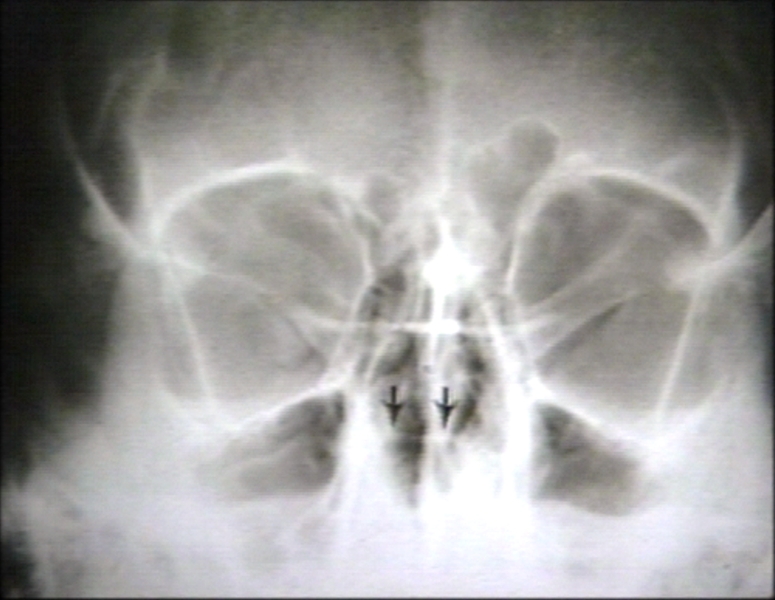

RADIOLOGY: SKULL: SELLA TURCICA, NORMAL, ANATOMY; SELLA FLOOR WITH ARROWS (PLAIN FILM)